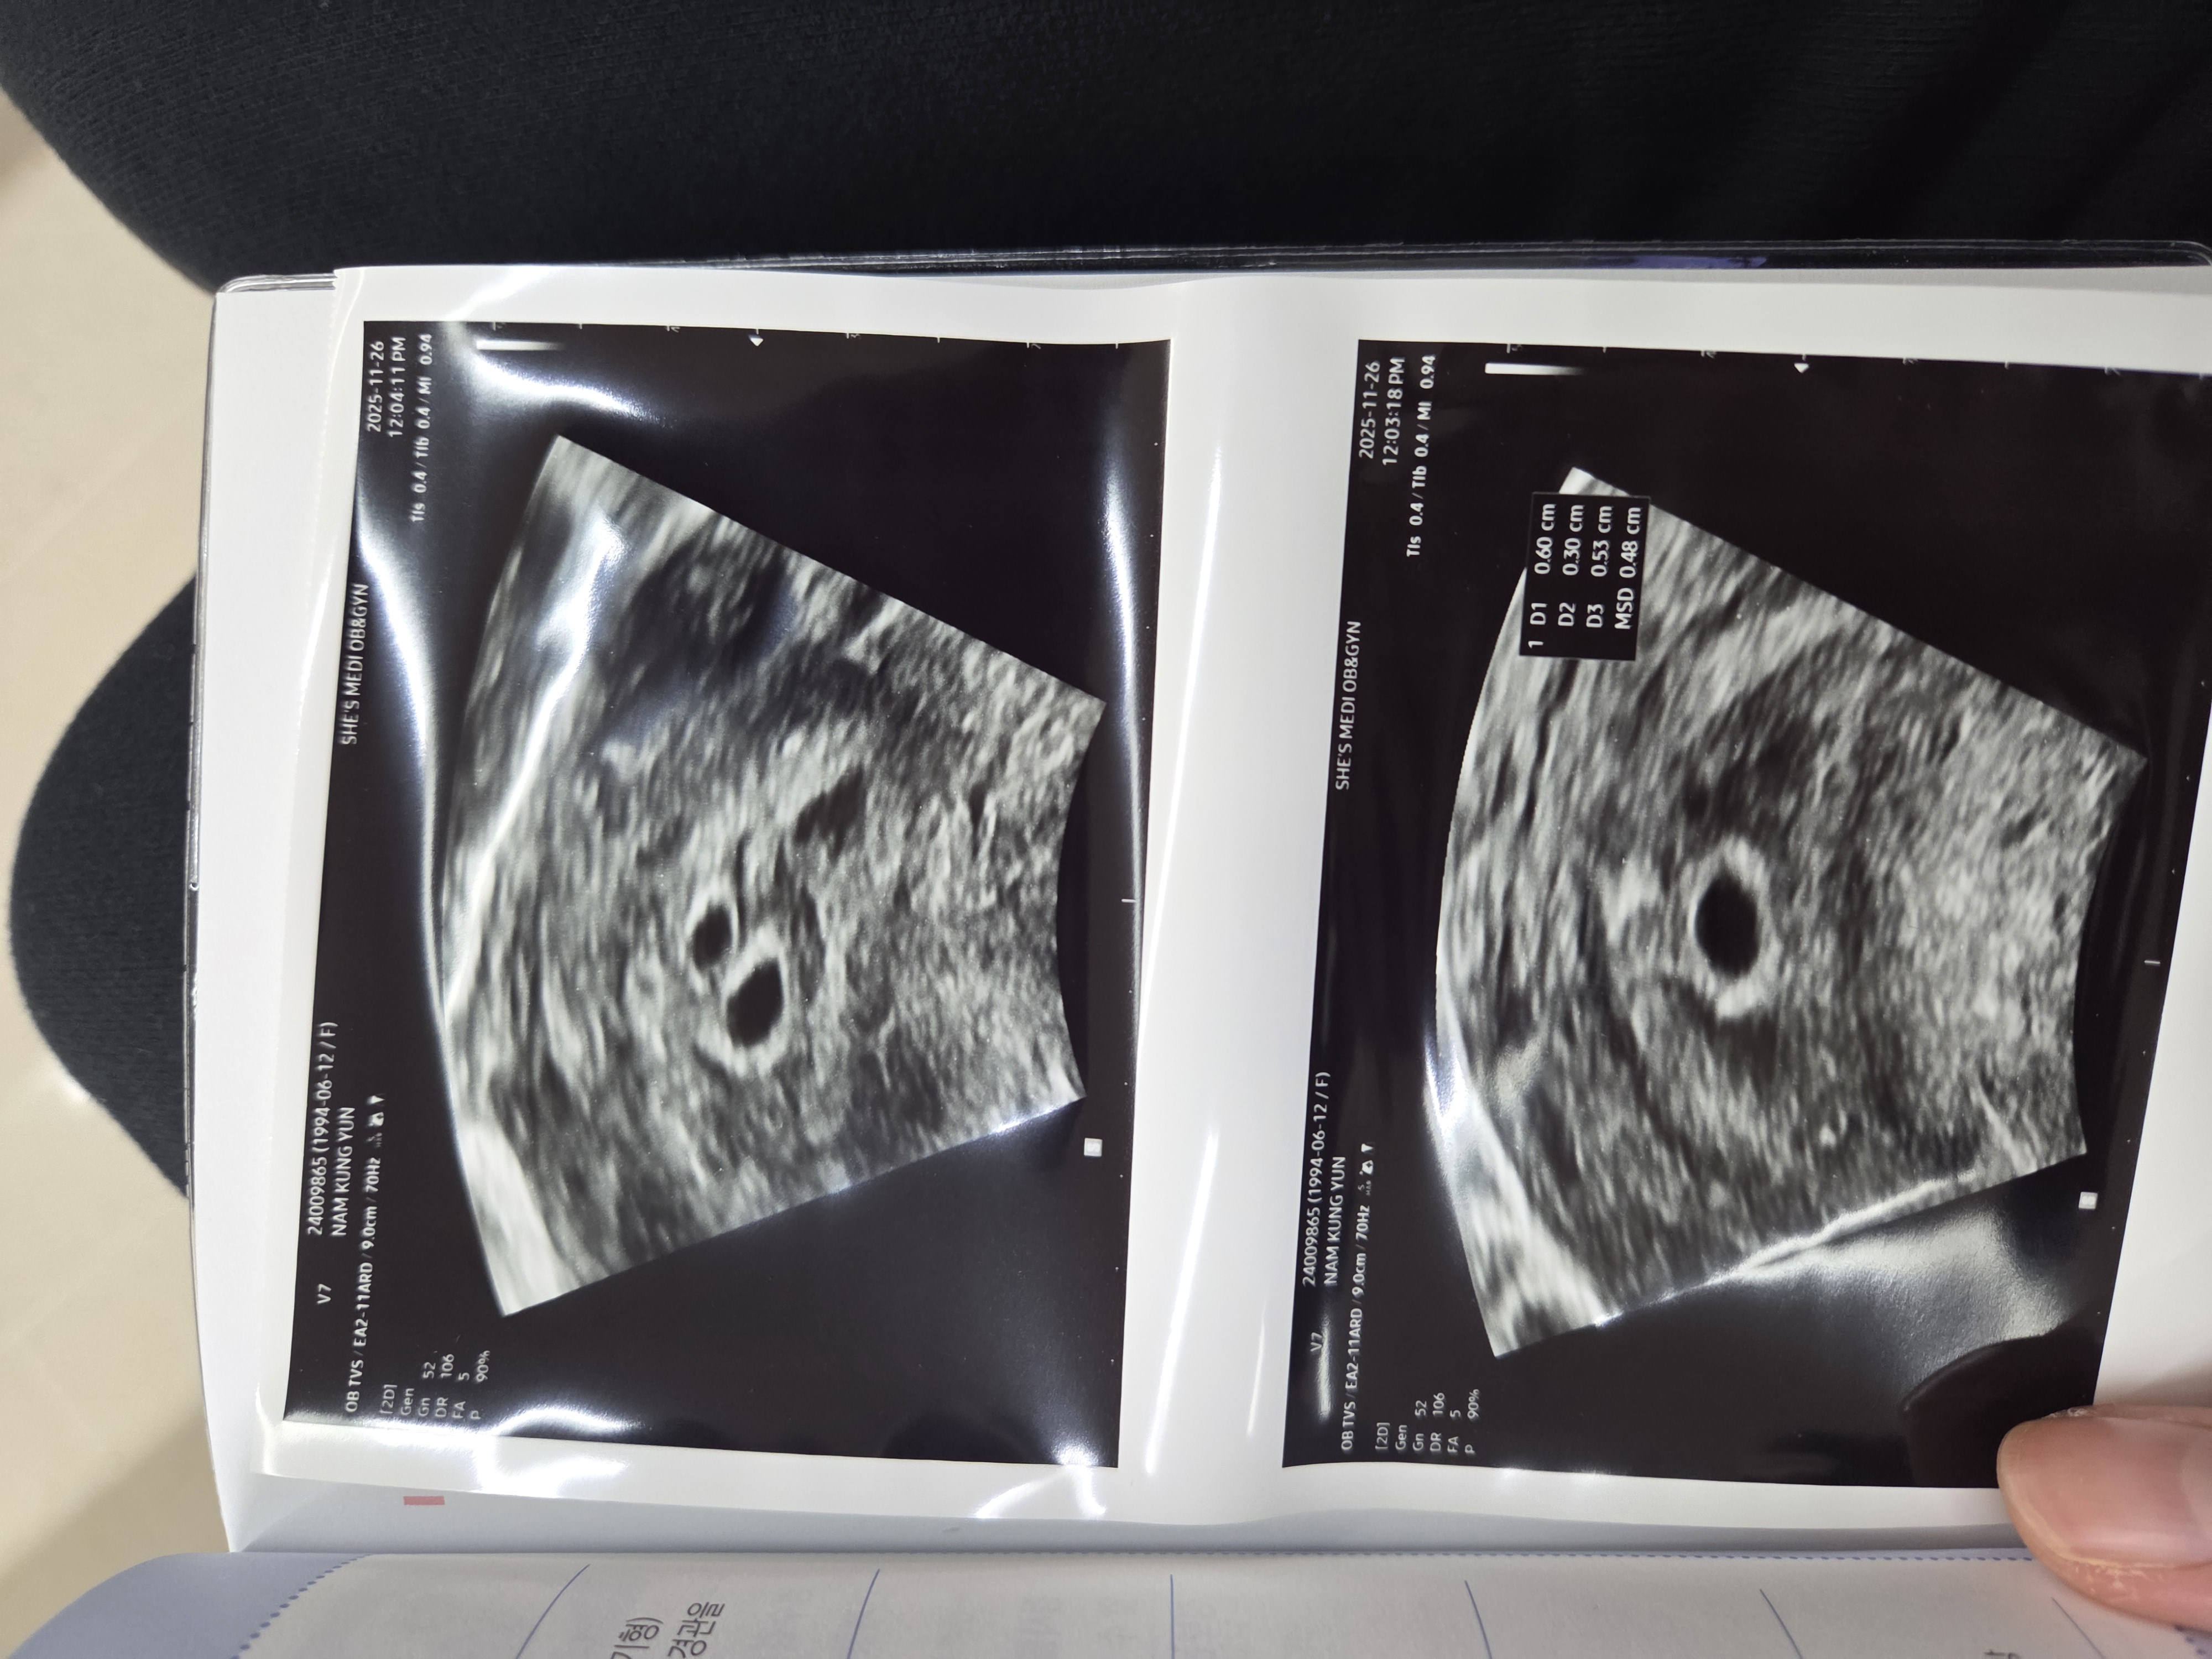

오늘 초음파 보고왔는데 아기집이 두개같다고 하셨어요! 피고임일 수도있지만... 2주뒤에 다시 확인해보자고 하셨어요! 쌍둥이일까요..?

아기집 맞는거같아요..!!!!